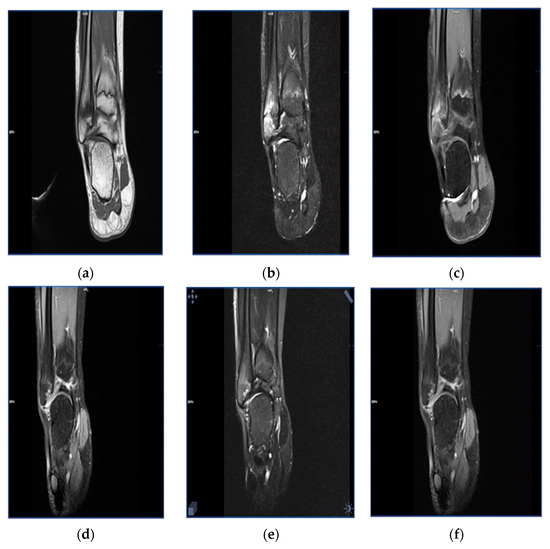

The duration of follow-up of the study patients varied between 3 months and 3 years. In 40% of the patients, both clinical symptoms and radiological abnormalities resolved completely, whereas another 50% of patients showed partial regression of clinical and radiological manifestations. In the remaining 10% of the patients, follow-up was too short to confirm progression/regression of the disease (Figure 2, Figure 3 and Figure 4).

Figure 3. Magnetic resonance images in a 13-year-old female patient with bone marrow edema within the head of the fibula. Status before treatment: T1-weighted sequence (a), T2-weighted sequence (b), T1-weighted sequence with contrast enhancement (c). Status after a 15-month follow-up, with regression of the bone marrow edema: T1-weighted sequence (d), T2-weighted sequence (e), T1-weighted sequence with contrast enhancement (f).

All patients with a presumptive diagnosis of CRMO underwent MRI (Table 3). Most patients presented with multifocal hypodense areas on T1-weighted images, with the enhancement of signal on T-weighted and STIR sequences. Additionally, the areas involved with the inflammatory process showed an intensive contrast enhancement. Furthermore, MRI demonstrated swelling of adjacent soft tissues and bone marrow edema. The abnormalities described above, in particular bone lesions, were found in all patients diagnosed with CRMO. Typical MRI findings in the thoracic and lumbar spine included the decreased height of vertebral bodies and bone marrow edema.

MRI also remains the most accurate diagnostic option in patients with relapse. In 30% of patients included in this study, MRI demonstrated progression of primary foci as well as secondary foci, usually in the proximity of the primary foci or in the thoracic/lumbar spine. Clinically, such patients presented with pain of the involved anatomical area and/or impaired function of adjacent joints. Our study also confirmed the role of MRI as a gold diagnostic standard in patients with remission. In such patients, MRI showed a substantial decrease in the size of inflammatory foci within the bone, regression of bone marrow edema and resolution of lesions in adjacent soft tissues. Such radiological presentation correlated with partial or complete remission of clinical symptoms.